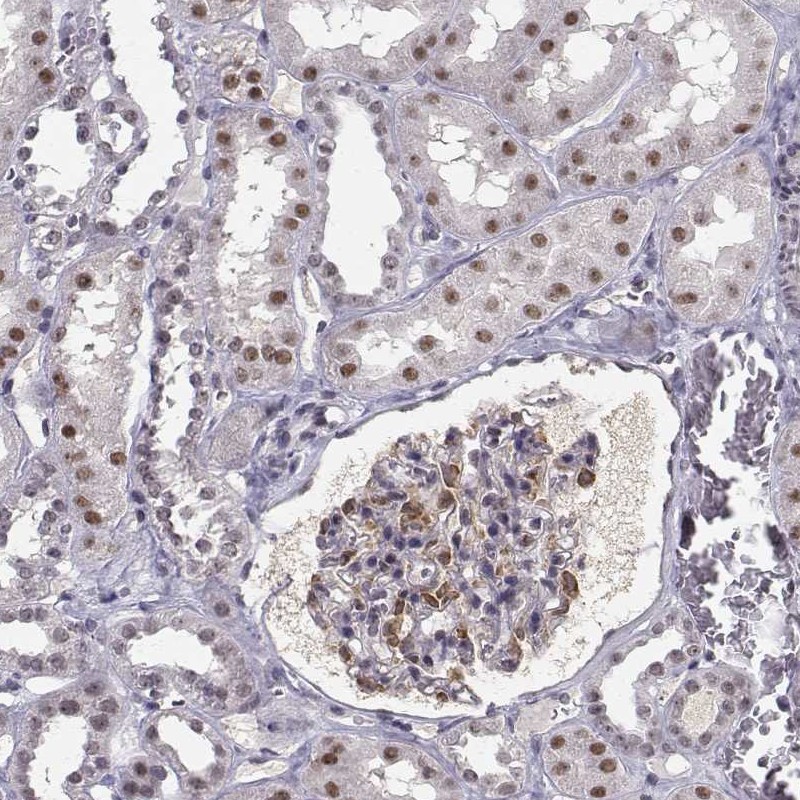

Immunohistochemical staining of human kidney shows strong nuclear positivity in cells in glomeruli and cells in tubules.